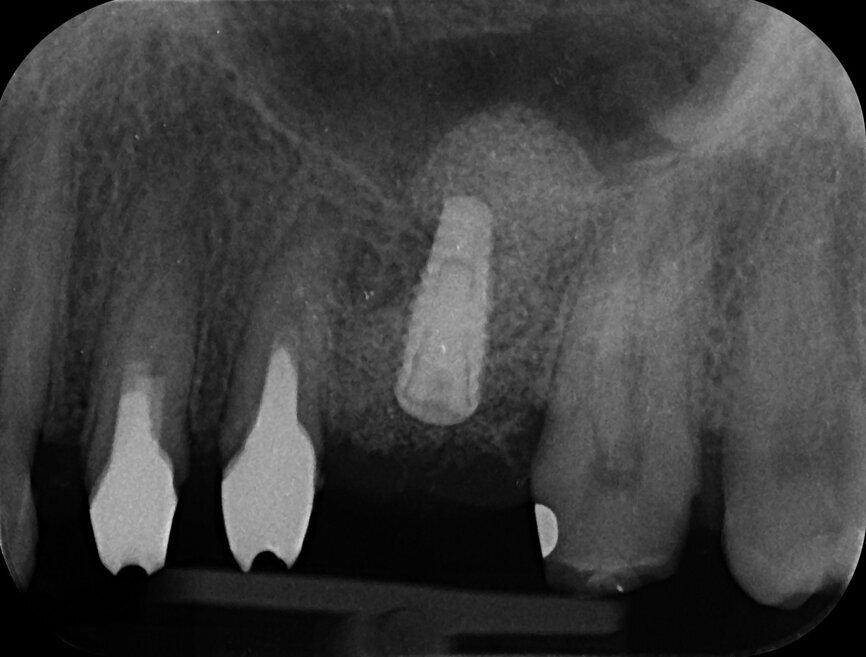

The patient who is the focus of our discussion came to our office reporting intense pain in response to hot and cold stimuli in the left maxilla (Fig. 1). He described the pain as being spontaneous at times and that in order for it to subside administration of anti-inflammatory medication was required. Upon examination, an accurate diagnosis was established of symptomatic irreversible pulpitis affecting tooth #27. The patient had had the tooth prepared for a crown sometime in the last 60 days (Fig. 2), but unfortunately the treatment was not completed for unknown reasons. Caries seemed to be absent; therefore, a minimally invasive approach was planned. Most likely, the pathology was caused by either trauma or an iatrogenic event.

After isolation of the tooth (Fig. 3), an access cavity was created using high-speed diamond burs and ultrasonic tips (Figs. 4–8). Pre-flaring in the coronal and middle thirds was done with the HyFlex EDM 25 instrument (at a torque of 4 Ncm and a speed of 500 rpm). It is a proven fact that pre-flaring allows an increase in the instrument size that binds in the root canal, irrespective of the discrepancy between the size of the file and anatomical diameter. [19–21] Afterwards, canal scouting was performed using an ISO size 10 stainless-steel K-file up to working length. Upon establishing the working length, with the help of an apex locator, the 10/05 EDM file (glide path file) was used up to working length (at a torque of 3 Ncm and a speed of 300 rpm). Subsequently before finishing the preparation with the 25 EDM file, the 20/05 EDM (preparation file) was used to full working length (at a torque of 3 Ncm and a speed of 400 rpm). At this point, the working length was confirmed again with an ISO size 20 NiTi K-file. Root canal shaping was completed with the 25 EDM file, which was inserted to full working length (at a torque of 3 Ncm and a speed of 400 rpm; Figs. 9–12).